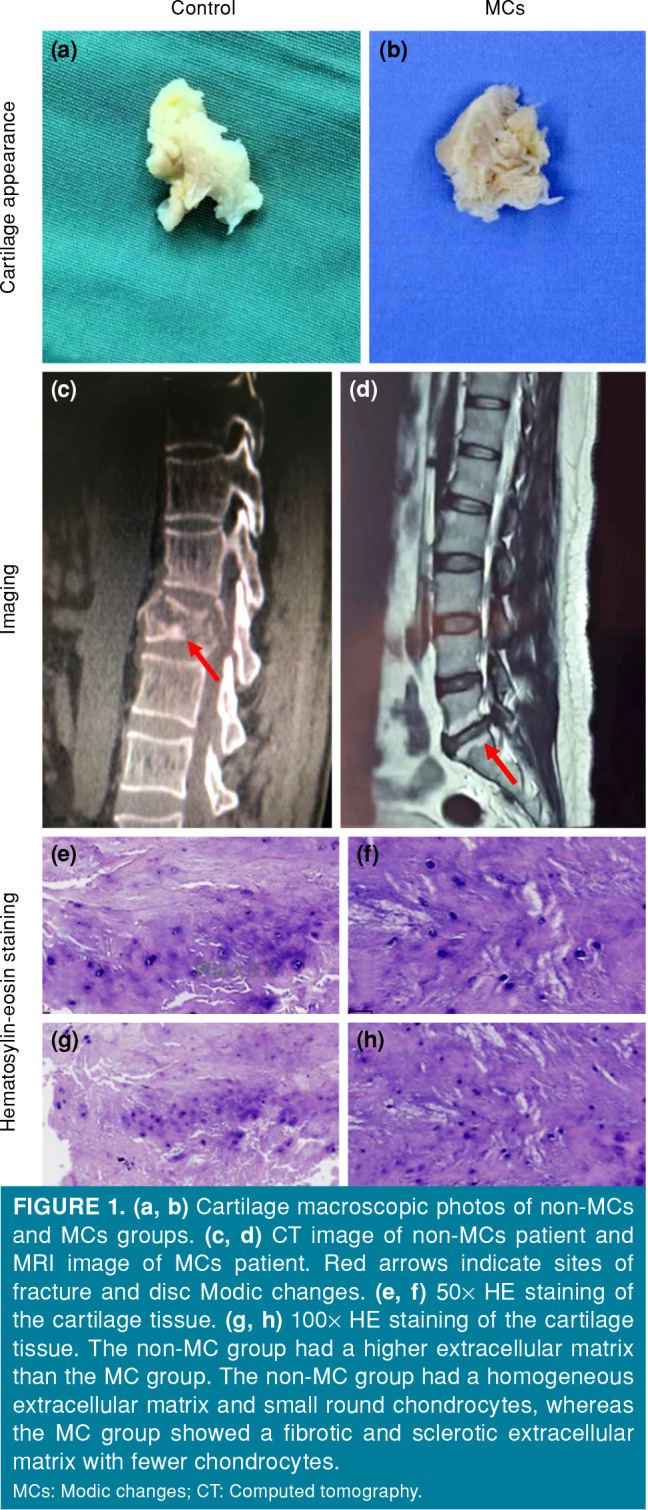

Results: There were no significant differences in the baseline characteristics between the two groups. The color and transparency of the endplate cartilage in the control group were significantly better than those in the MCs group. Radiographic and hematoxylin-eosin staining of the endplate cartilage tissues showed that the extracellular matrix was higher in the control group than in the MCs group (p<0.05). Compared to the control group, qPCR analysis showed higher expression of MMP-1 and ADAMTS-5 in the MCs group, while aggrecan expression was lower (p<0.05). Western blot analysis showed that both MMP-1 and ADAMTS-5 expression were higher in the MCs group than in the control group (p<0.05).

{"title":"Expression of lipid metabolism and cartilage degeneration-related factors in lumbar vertebral endplate Modic changes.","authors":"Congjie Li, Di Li, Xiaowei Yao, Shaosong Sun, Bao Ren, Ye Han","doi":"10.52312/jdrs.2025.1870","DOIUrl":null,"url":null,"abstract":"<p><strong>Objectives: </strong>This study aims to investigate the relationship between the expression of lipid metabolism and cartilage degeneration-related factors and Modic changes (MCs) of lumbar vertebral.</p><p><strong>Patients and methods: </strong>This prospective study included a total of 10 patients (6 males, 4 females; mean age: 60.4±8.7 years; range 51 to 82 years) who underwent lumbar interbody fusion surgery due to degenerative lumbar diseases (MC group), and 10 control patients (4 males, 6 females; mean age: 49.7±9.8 years; range, 42 to 76 years) with lumbar burst fractures (nonMC group) between January 2020 and December 2022. Clinical imaging data and cartilage tissues were collected to observe cartilage characteristics and pathological changes. The relative expression levels of lipid metabolism-related inflammatory factors matrix metalloproteinase-1 (MMP-1), a disintegrin and metalloproteinase with thromboSpondin motifs-5 (ADAMTS-5), and aggrecan in cartilage were detected by quantitative polymerase chain reaction (qPCR). The relative expression levels of MMP-1 and ADAMTS-5 proteins in cartilage tissues were detected by Western blotting.</p><p><strong>Results: </strong>There were no significant differences in the baseline characteristics between the two groups. The color and transparency of the endplate cartilage in the control group were significantly better than those in the MCs group. Radiographic and hematoxylin-eosin staining of the endplate cartilage tissues showed that the extracellular matrix was higher in the control group than in the MCs group (p<0.05). Compared to the control group, qPCR analysis showed higher expression of MMP-1 and ADAMTS-5 in the MCs group, while aggrecan expression was lower (p<0.05). Western blot analysis showed that both MMP-1 and ADAMTS-5 expression were higher in the MCs group than in the control group (p<0.05).</p><p><strong>Conclusion: </strong>Lipid metabolism and cartilage degeneration-related inflammatory factors exist in the vertebral endplate of the patients with degenerative lumbar diseases, and the upregulation of MMP-1 and ADAMTS-5 may be related to MCs and endplate degeneration.</p>","PeriodicalId":73560,"journal":{"name":"Joint diseases and related surgery","volume":"36 1","pages":"39-46"},"PeriodicalIF":1.9000,"publicationDate":"2025-01-02","publicationTypes":"Journal Article","fieldsOfStudy":null,"isOpenAccess":false,"openAccessPdf":"https://www.ncbi.nlm.nih.gov/pmc/articles/PMC11734858/pdf/","citationCount":"0","resultStr":null,"platform":"Semanticscholar","paperid":null,"PeriodicalName":"Joint diseases and related surgery","FirstCategoryId":"1085","ListUrlMain":"https://doi.org/10.52312/jdrs.2025.1870","RegionNum":0,"RegionCategory":null,"ArticlePicture":[],"TitleCN":null,"AbstractTextCN":null,"PMCID":null,"EPubDate":"2024/12/18 0:00:00","PubModel":"Epub","JCR":"Q2","JCRName":"ORTHOPEDICS","Score":null,"Total":0}